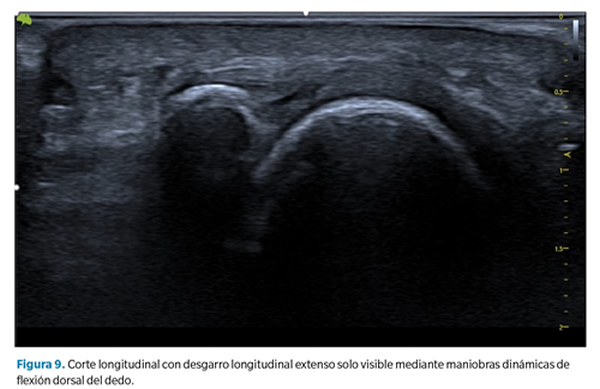

- Aplanamiento y atenuación de la placa plantar. En estos casos no se observa un defecto de forma tan clara, pero debe llamarnos la atención cuando la zona de inserción, generalmente más gruesa, se aprecia más adelgazada que la zona media o proximal de la placa. Esto sugiere generalmente la presencia de un desgarro transversal que abarca desde la porción lateral hasta la porción central de la placa40 (Figura 9).

Como se ha señalado, en todos los casos las maniobras dinámicas de tensión del dedo (y la placa) son esenciales para establecer la presencia o no de un desgarro y su magnitud41,42. La incapacidad de tensar la placa (pasar de su estado curvado a un estado lineal) así como la pérdida de movimiento congruente entre la falange proximal y la placa son signos muy sugerentes de desgarro que solo pueden apreciarse mediante dichas maniobras.